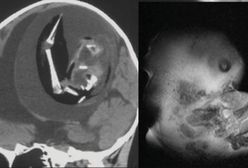

Nienarodzony bliźniak był w mózgu siostry. Został usunięty

Płód nieradzonego bliźniaka rozwinął się w mózgu jednorocznego dziecka. Takiego odkrycia dokonali lekarze z Szanghaju, którzy przyjęli do szpitala dziewczynkę z opóźnieniem motorycznym oraz powiększonym obwodem głowy. Pasożytniczy płód został chirurgicznie usunięty z czaszki dziecka.